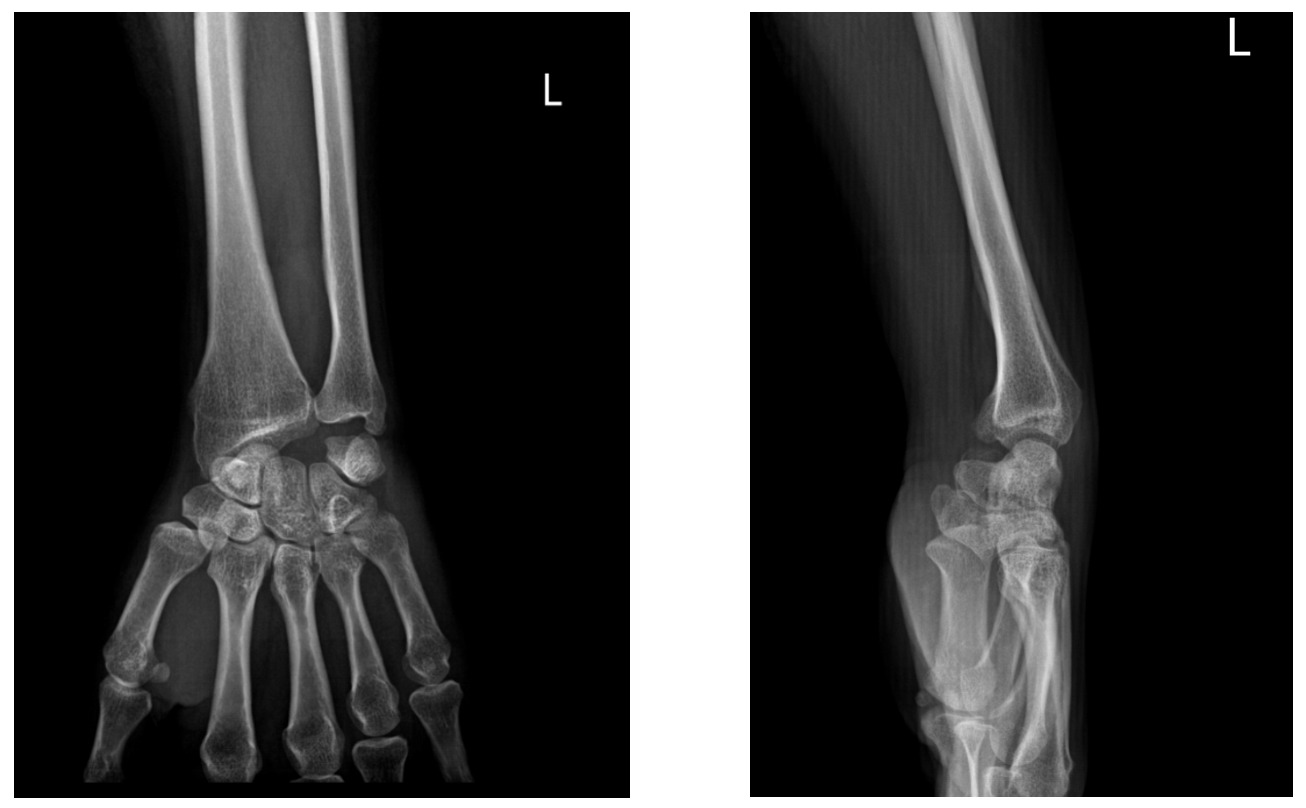

A 45-year-old woman sustained a left wrist injury in 2020 after a fall onto an outstretched hand. She was evaluated at a local facility, but a left lunate dislocation was missed. Two weeks prior to admission she developed atraumatic loss of active flexion of the left III and IV fingers. On examination, injury to the left flexor tendons of digits III and IV was suspected. Radiographs and CT scan demonstrated a volar dislocation of the lunate. The patient underwent surgery on October 1, 2024.

Through a volar approach, we identified ruptures of the FDP to digits III and IV and of the FDS to digit IV at the level of the volar lunate dislocation. The FDP tendons to digits III and IV were retracted with a 2-cm segmental defect and poor tendon quality, precluding direct end-to-end repair. The FDS to digit IV was retracted ~1 cm with good tendon quality. We therefore performed excision of the lunate, FDP reconstruction for digits III and IV using an autologous palmaris longus tendon graft with Pulvertaft technique, and direct repair of the FDS to digit IV using modified Kessler technique.

In our patient, the lunate dislocation had been neglected for 4 years. Preoperative radiographs and CT showed no radiocarpal degenerative changes. Intraoperatively, the FDS to digit IV had a short retraction with good tendon quality, allowing direct end-to-end repair; by contrast, the FDP to digits III and IV were retracted (~2 cm) with poor-quality ends. Accordingly, we performed lunate excision, direct repair of the FDS to digit IV, and reconstruction of the FDP to digits III and IV using an autologous palmaris longus tendon graft.